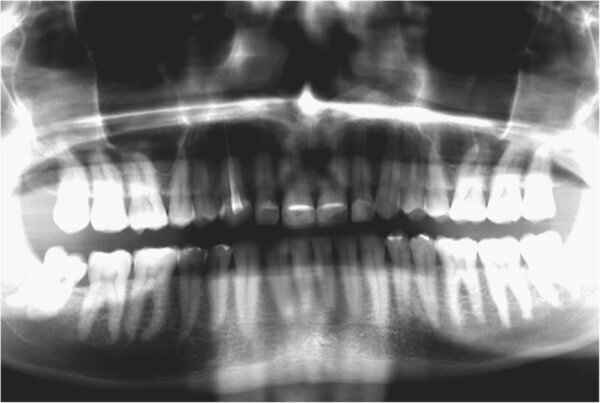

Fig. 15. Imagen panorámica final.

Se retiró el exceso de material de fijación, y la oclusión se adaptó y verificó con la tecnología T-Scan (Tekscan). Se usó una férula de resina acrílica removible para proteger las restauraciones finales. Las restauraciones finales se verifican después de seis meses. Las restauraciones estaban estables y no mostraban signos de fractura (Figs. 13-15). El paciente también informó que ya no sufría dolores de cabeza con la nueva altura de la mordida.